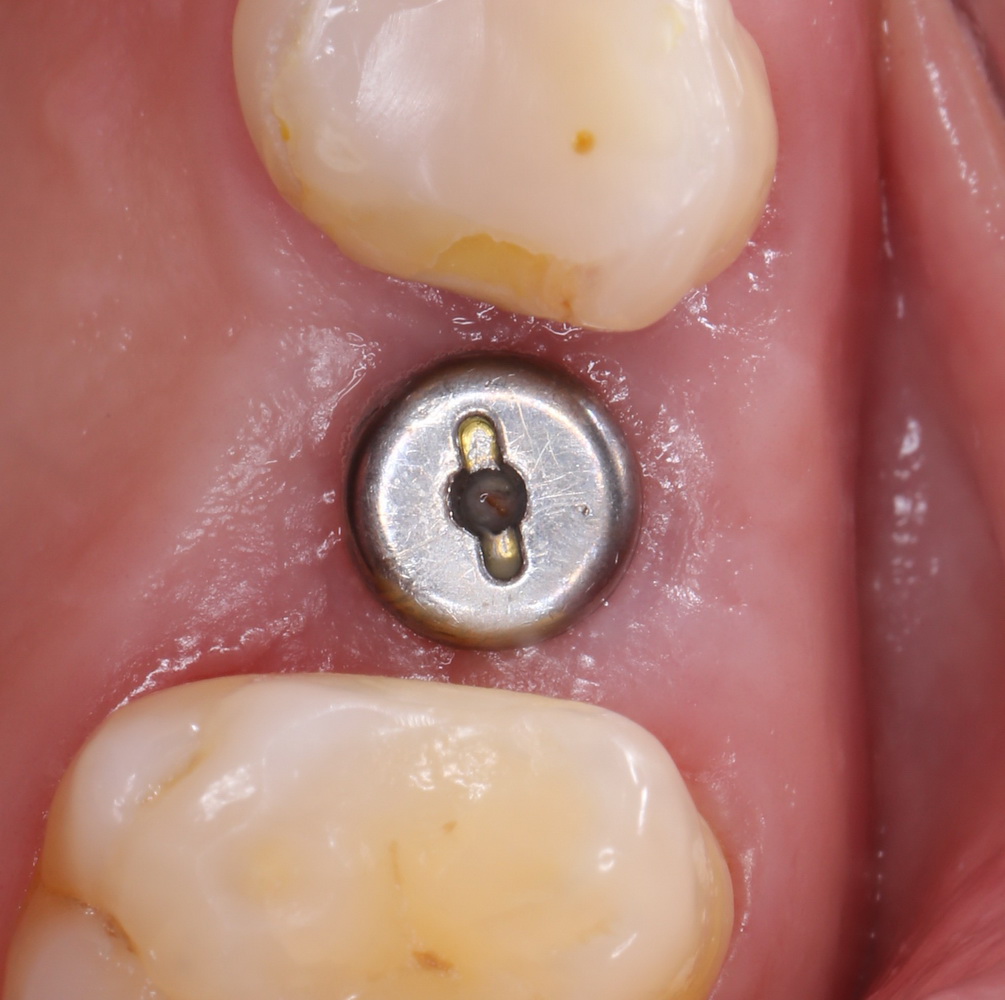

На приведенных фотографиях заметно, как изменились линейные размеры альвеолярного гребня с момента удаления 26 и установки импланта, до его интеграции (сравните толщину). Но это не так критично, и позволяет получить хороший результат протезирования:

Через 4 месяца клиническая ситуация выглядит подобным образом:

мы можем спокойно приступить к формированию десны:

Через неделю можно снять швы. Область раны выглядит следующим образом:

А через два месяца — вот так:

На этом этапе, для создания более правильного десневого контура, можно поменять формирователь размер больше: